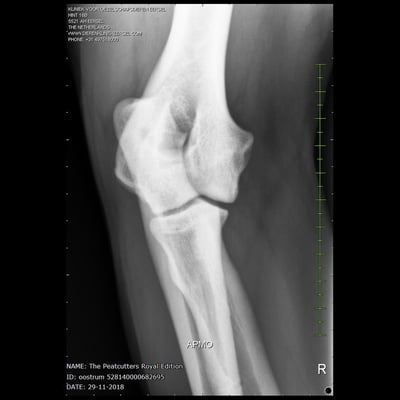

Sjors his official hip and elbow results with the photos. X-rayed at 20 months of age. HD-C, ED-0.